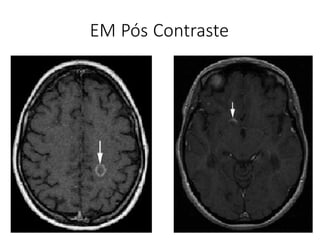

EM Pós Contraste